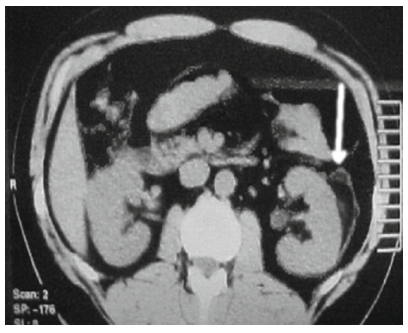

9

Hình 9. Tụ máu dưới bao thận sau TSNCT